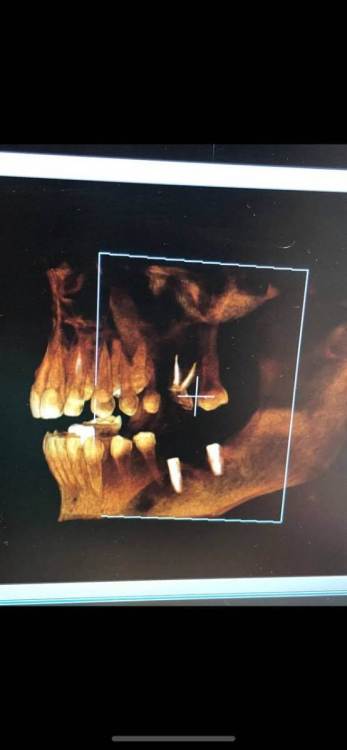

Stoyana Опубликовано 22 мая, 2023 Поделиться Опубликовано 22 мая, 2023 Здравствуйте ! Прошу прокомментировать замену имплантов . 10 лет назад были установлены 2 импланта , 6 на место удаленного зуба , и 7 - в качестве антагониста верхней 7 . Устанавил тот же доктор , по гарантии . Приняли решение заменить импланты , так как коронка с 6 сломалась , на 7 сломался абатмент . После операции , очень болит 5 , ноющая боль , плюс болезненные ощущения при глотании , болит челюсть в области операции . Доктор утверждает что по снимку проблем нет . Прошу прокомментировать ситуацию . Первые 2 фото - импланты которые заменили . 3 и 4 фото - новые импланты Ссылка на комментарий